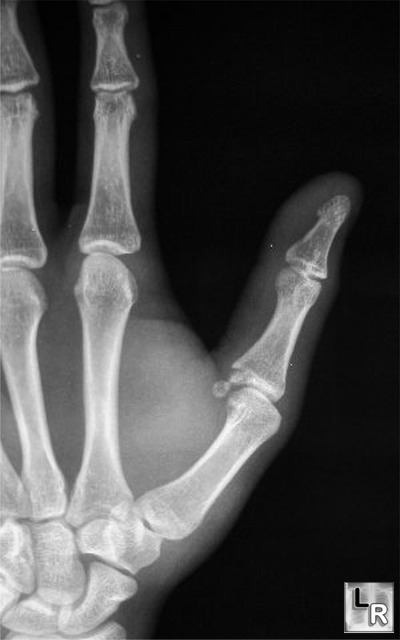

指の骨は,中手骨と指骨に分けられます。 中手骨は,手根骨に近い方であり指骨は指先の方です。 指骨は,基節骨・中節骨・末節骨に分けられます。 後遺障害(後遺症)となるのは, 手の指が痛い9(末節骨骨折) あなたの診断は? 昨日のうちはズキズキするような痛みがあったようです。 でも今日はその痛みは無くなったが、見た目に骨折している a基節骨骨折 1. 骨幹部骨折 (変形)掌側凸変形 近位骨片:屈曲(虫様筋、骨間筋) 遠位骨片:背側(背側腱膜) (整復) MP関節屈曲させ両母指で基節骨を掌側から圧

基節骨骨折 末節骨骨折などの指骨骨折の症状 治療法 骨 筋肉 関節の病気 All About